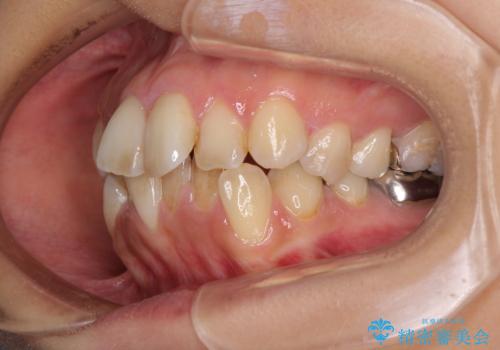

デコボコと口元の突出感 ハーフリンガルでの抜歯矯正

- 矯正装置

- ハーフリンガル

- 前歯のデコボコと上顎の前突感による口の閉じにくさを気にして来院された患者様です。

目立たない装置を希望されたので、上顎が裏側装置のハーフリンガルを選択し、上下左右の小臼歯(計4歯)を抜歯して矯正治療を行うこととしました。